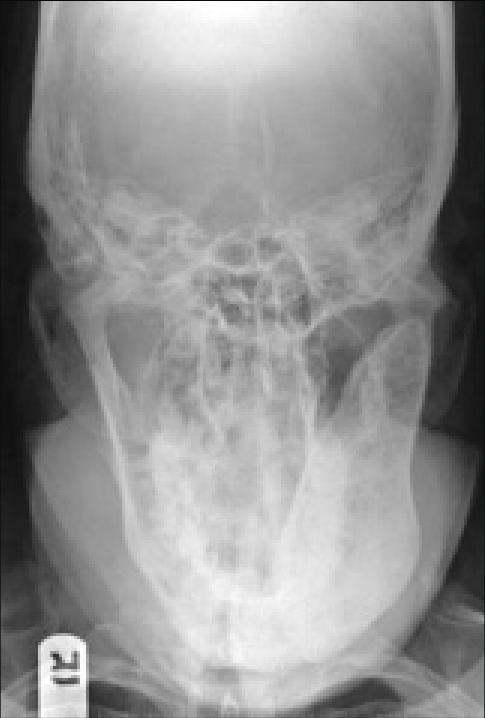

What is the towne's veiw of the skull?

The anterior-posterior view where pt facing away from receptor and chin tilted down -30 degrees